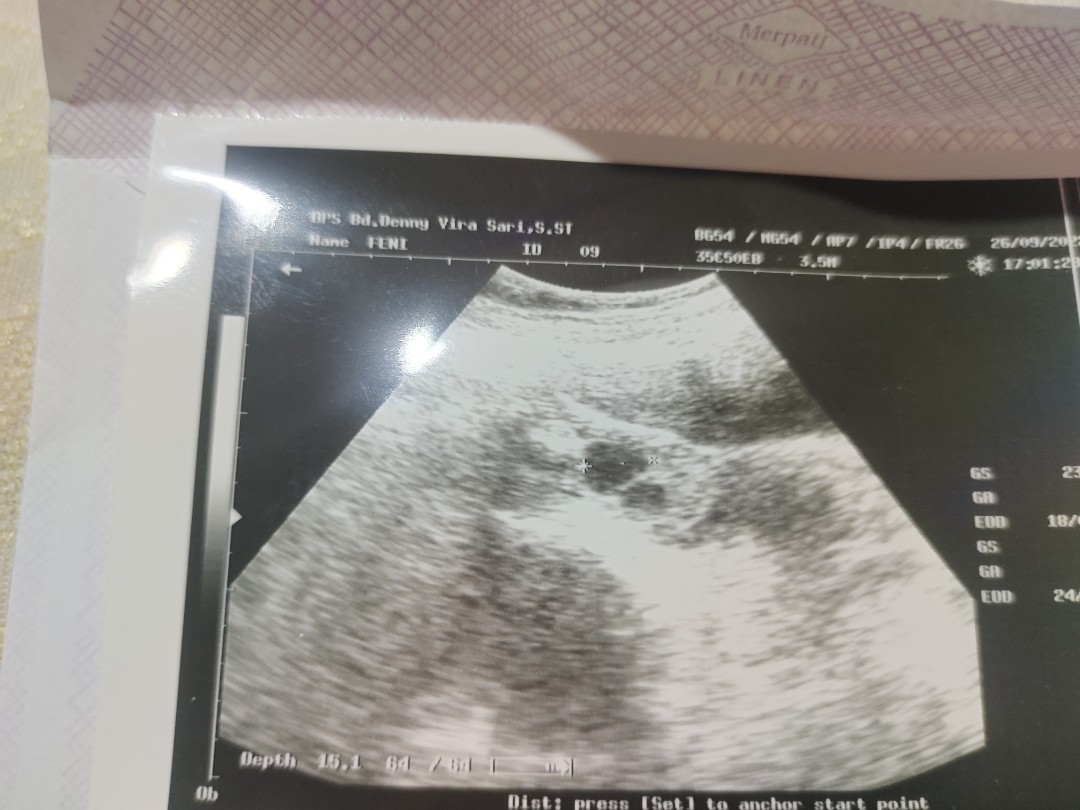

ini hasil USG ku dokter menyatakan kembar saat itu, dan disarankan untuk USG ulang dibulan berikutnya buat memastikan hasilnya yg lebih jelas lagi. doain ya bunda² hasilnya baik dan sehat 🤲

Bisa ko bun bayi aku kembar pas usg keliatan ko kembarnya ini usia 7minggu ada dua kan itu kantungnya

sy pernh usg dpt sperti ini 6 week apa kah dua kantung bun ? bidan blm.brani mastiin